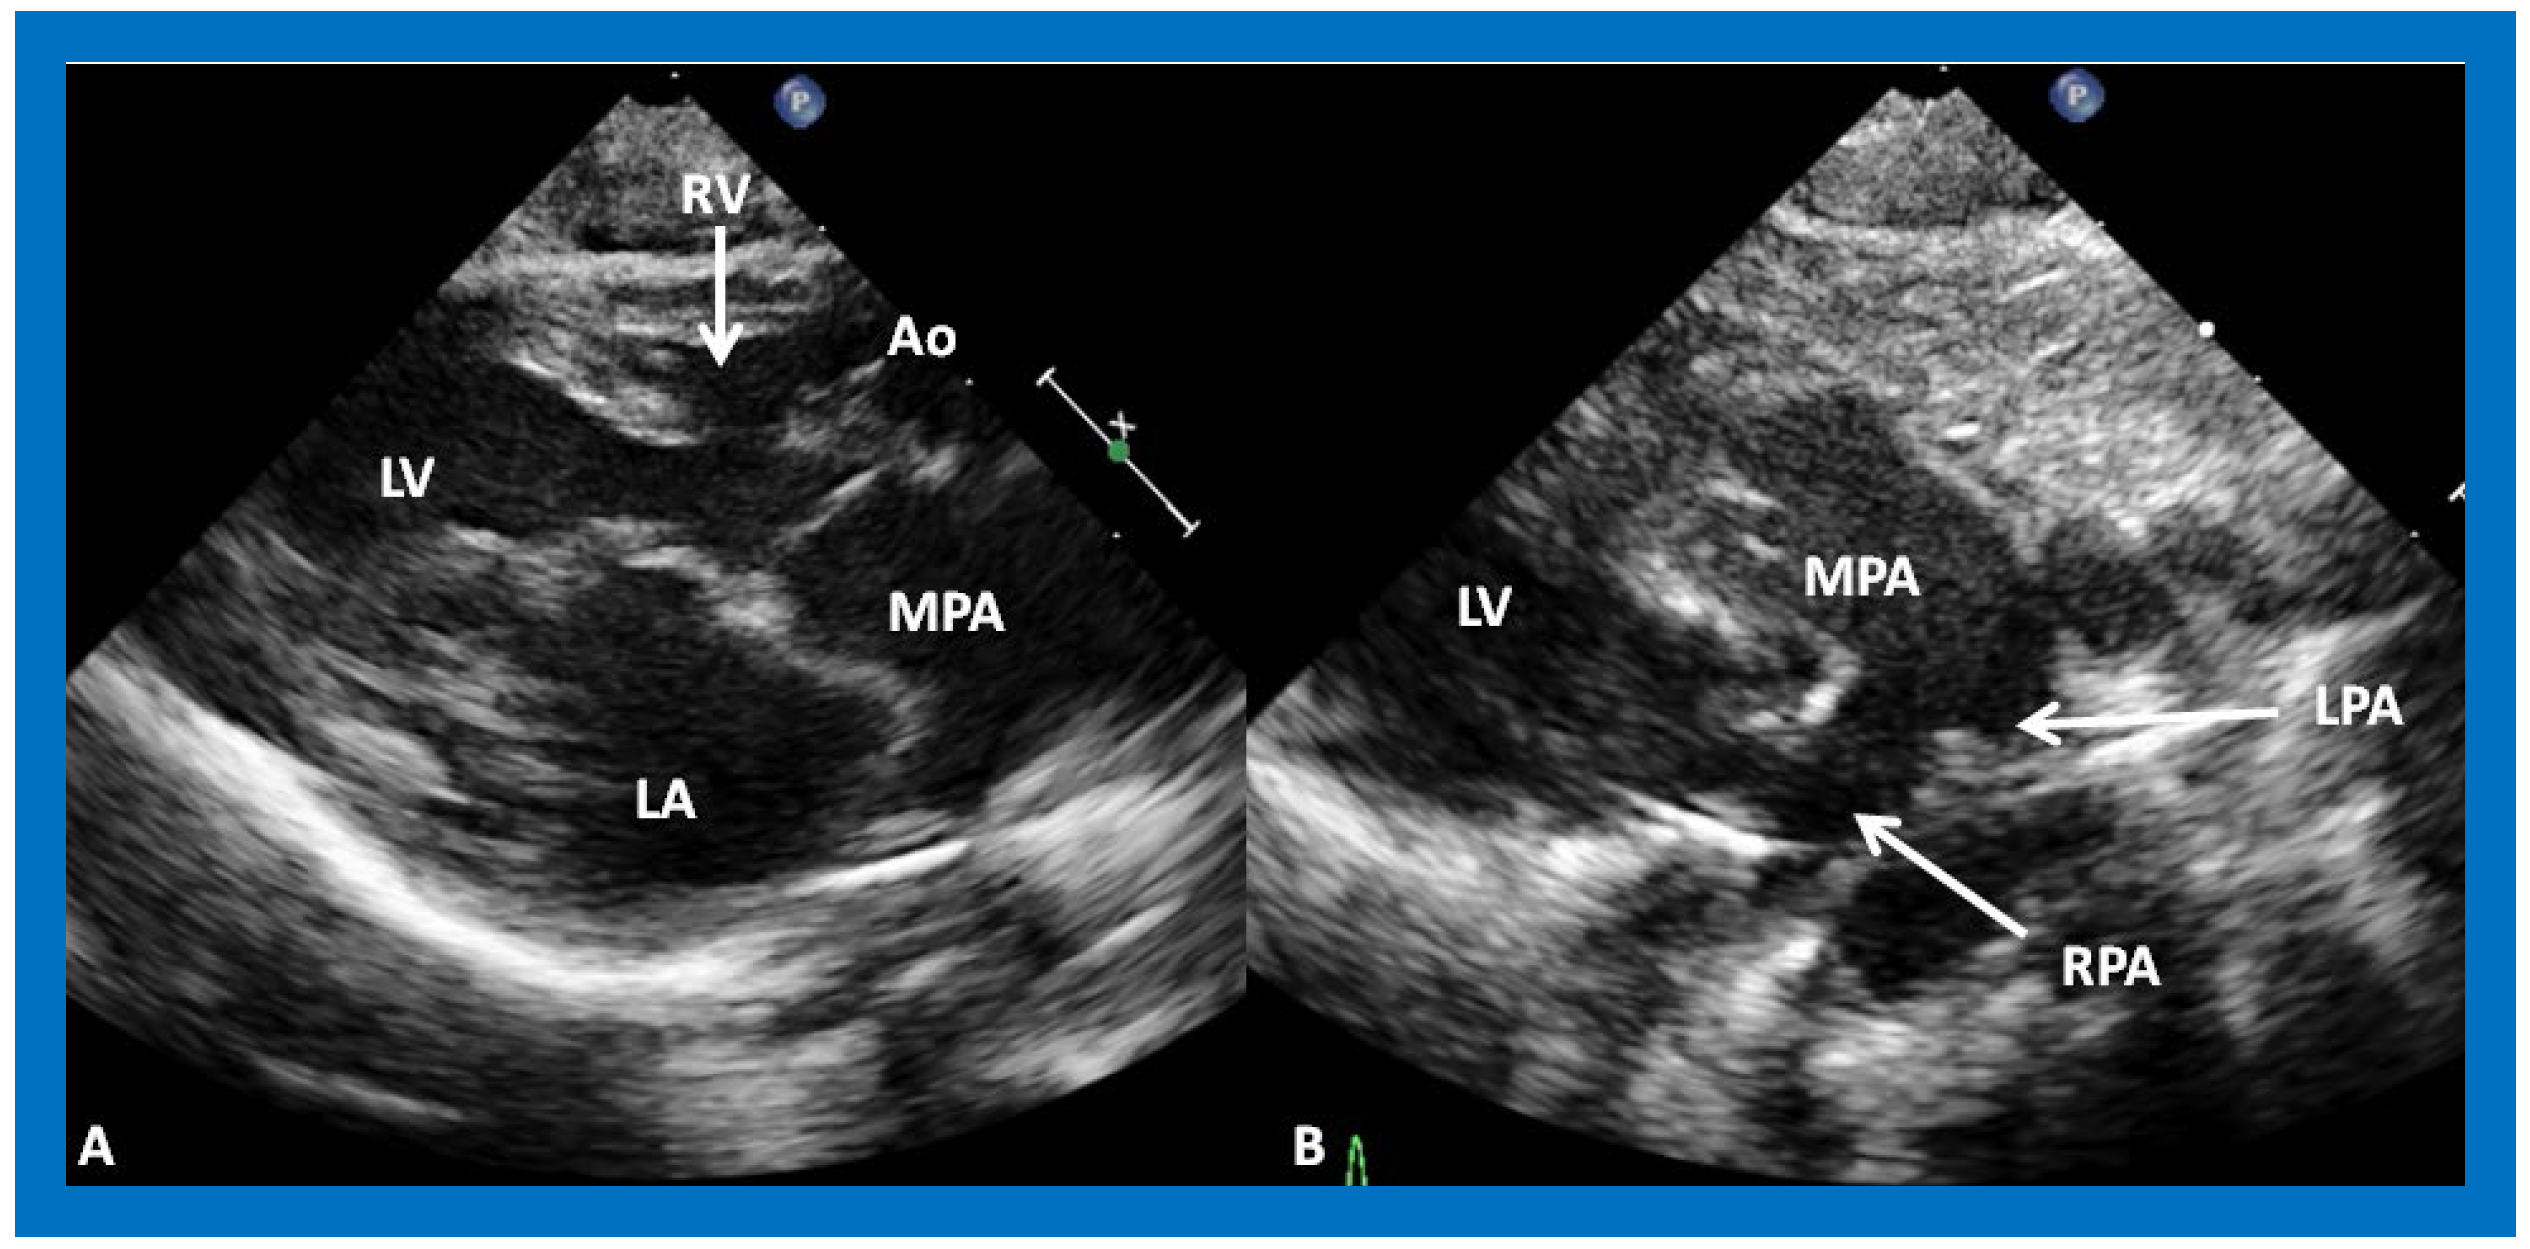

The relationship of the great arteries is examined next in order to classify them into various types, as mentioned above. The relationship of the great arteries (Figure 2, top) is established by following the vessels arising from the ventricles until the pulmonary artery (PA) bifurcation or aortic arch. In Type I patients with normally related great arteries, the aorta arises from the LV (Figure 10) and in Type II patients with transposition of the great arteries, the PA arises from the LV (Figure 11; Figure 12). In Type II patients, the blood vessel arising from the LV should be traced to demonstrate its branching into the right and left PAs (Figure 11; Figure 12). In Type III patients, it may be a little more difficult to assign the great artery relationship and, sometimes, other imaging studies, including angiography, may be needed to define the great artery relationship. In Type IV with truncus arteriosus, the limited data suggest that this can be performed by echocardiography (Figure 13; Figure 15). In the example shown [31], the atretic tricuspid valve (Figure 13a and Figure 14a), VSD (Figure 13b and Figure 14b), hypoplastic RV (Figure 14a), single vessel (truncus) arising from the heart (Figure 13c,d, and Figure 14c,d), and origin of the PA and its division into branch PAs (Figure 13d, and Figure 14c,d) were demonstrated.

Figure 11. (A) A selected video frame from parasternal long axis views of a patient with tricuspid atresia and transposition of the great arteries demonstrating the left atrium (LA), left ventricle (LV), a very small right ventricle (RV) and a moderate sized ventricular septal defect (not marked). The vessel coming off the LV is traced in (B) and shown to bifurcate into the left (LPA) and right (RPA) pulmonary arteries, confirming that this vessel is the main pulmonary artery (MPA), consistent with transposition of the great arteries. Ao, Aorta. Reproduced from Reference [29].

Applsci 11 09472 g011

Figure 12. A selected video frame from a parasternal long axis view with color flow mapping of another patient with tricuspid atresia and transposition of the great arteries demonstrating the left atrium (LA), left ventricle (LV), a small right ventricle (RV) and a moderate sized ventricular septal defect (VSD). The vessel coming off the LV bifurcates into right (RPA) and left (LPA) pulmonary arteries. Reproduced from Reference [29]. PA, pulmonary artery.

Applsci 11 09472 g012